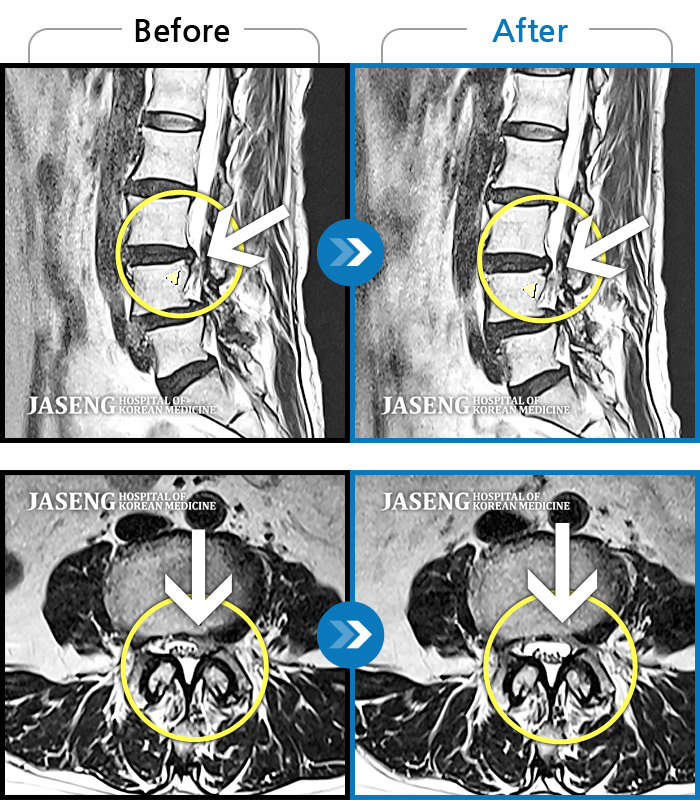

허리디스크

광주 · 김동은 원장

양측 허리부터 양측 골반까지 당기는 통증, 양측 하지 후면으로 이어지는 통증

촬영시기

2022.09.05 ~ 2024.05.06

2024.05.24